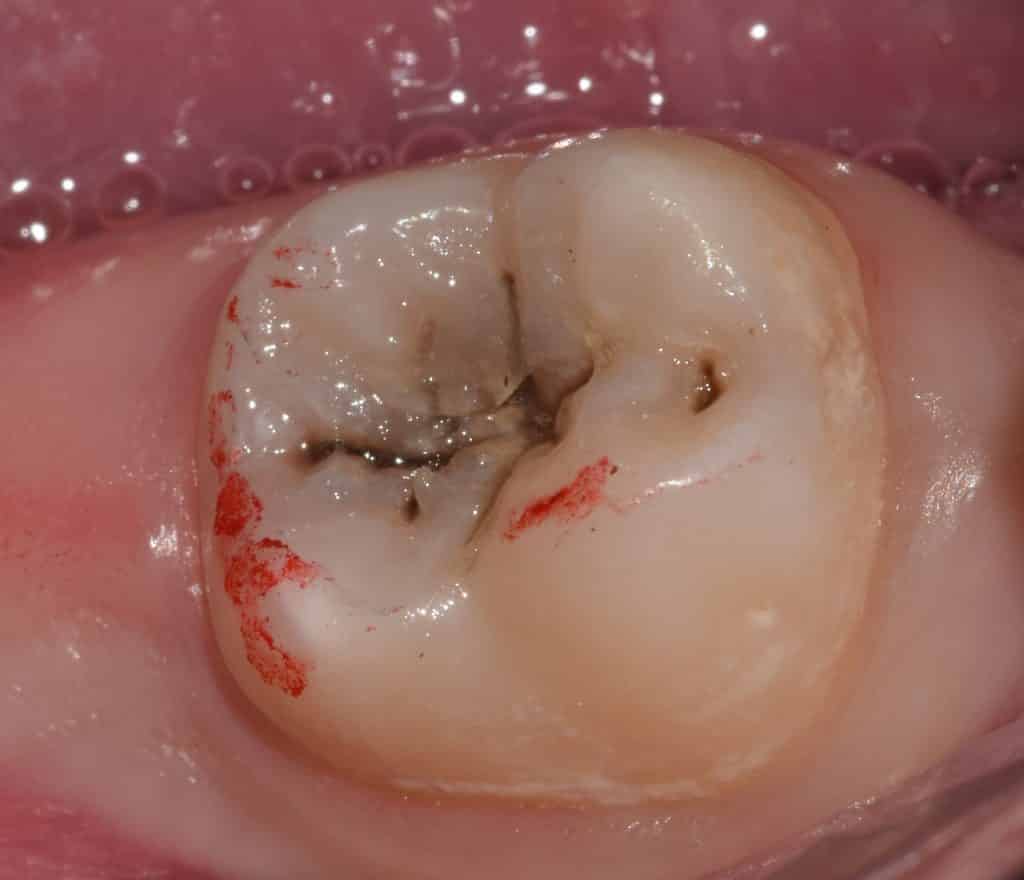

Caries removal and rubber dam application.

Then proceeding for etching, bonding, and composite layers application